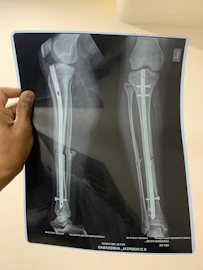

Orthopedic Procedures

From joint replacements to spinal corrections, regain strength, mobility, and confidence with internationally recognized orthopedic specialists. We prioritize safety, advanced techniques, and personalized rehabilitation in world-class clinics.